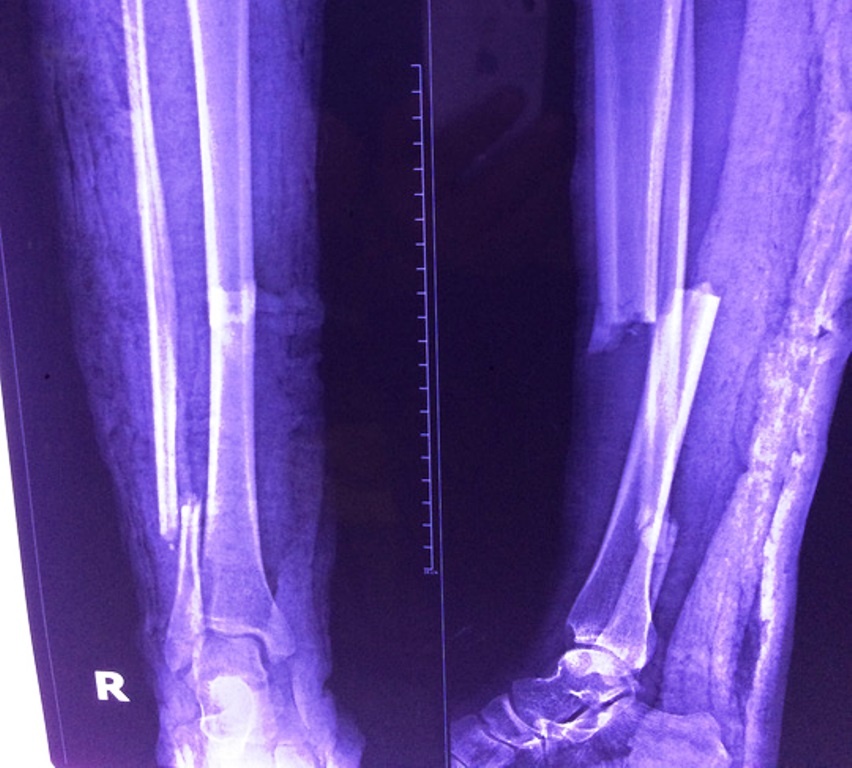

| Ảnh chụp phim X-quang người phụ nữ mắc bệnh tim bẩm sinh bị gãy chân. Ảnh: Phú Mỹ |

Chị Dung được chuyển vào bệnh viện quận 11 (TP.HCM). Bệnh viện đã hội chẩn nhiều chuyên khoa (ngoại chấn thương, tim mạch chuyển hóa, chẩn đoán hình ảnh, gây mê hồi sức....) kỹ càng và đưa đến quyết định mổ ghép xương cho bệnh nhân.

Bác sĩ Phạm Thanh Vũ, khoa Ngoại chấn thương, cho biết ê-kíp nhận định nếu gây tê toàn thân thì máu đổ về tim nhiều, khiến tim quá tải, co giãn quá sức gây nguy hiểm cho bệnh nhân. Ê-kíp đã gây gây tê vùng cẳng chân bệnh nhân dưới sự hướng dẫn của sóng siêu âm, nhằm giúp đưa thuốc tê chính xác vào dây thần kinh cần gây tê. Cách này không ảnh hưởng đến huyết động.

Ca phẫu thuật kéo dài gần 1 tiếng, các bác sĩ ghép xương thành công bằng phương pháp đinh nội tủy cố chốt. Bệnh nhân đã xuất viện vào ngày 9/10 sau một tuần điều trị.